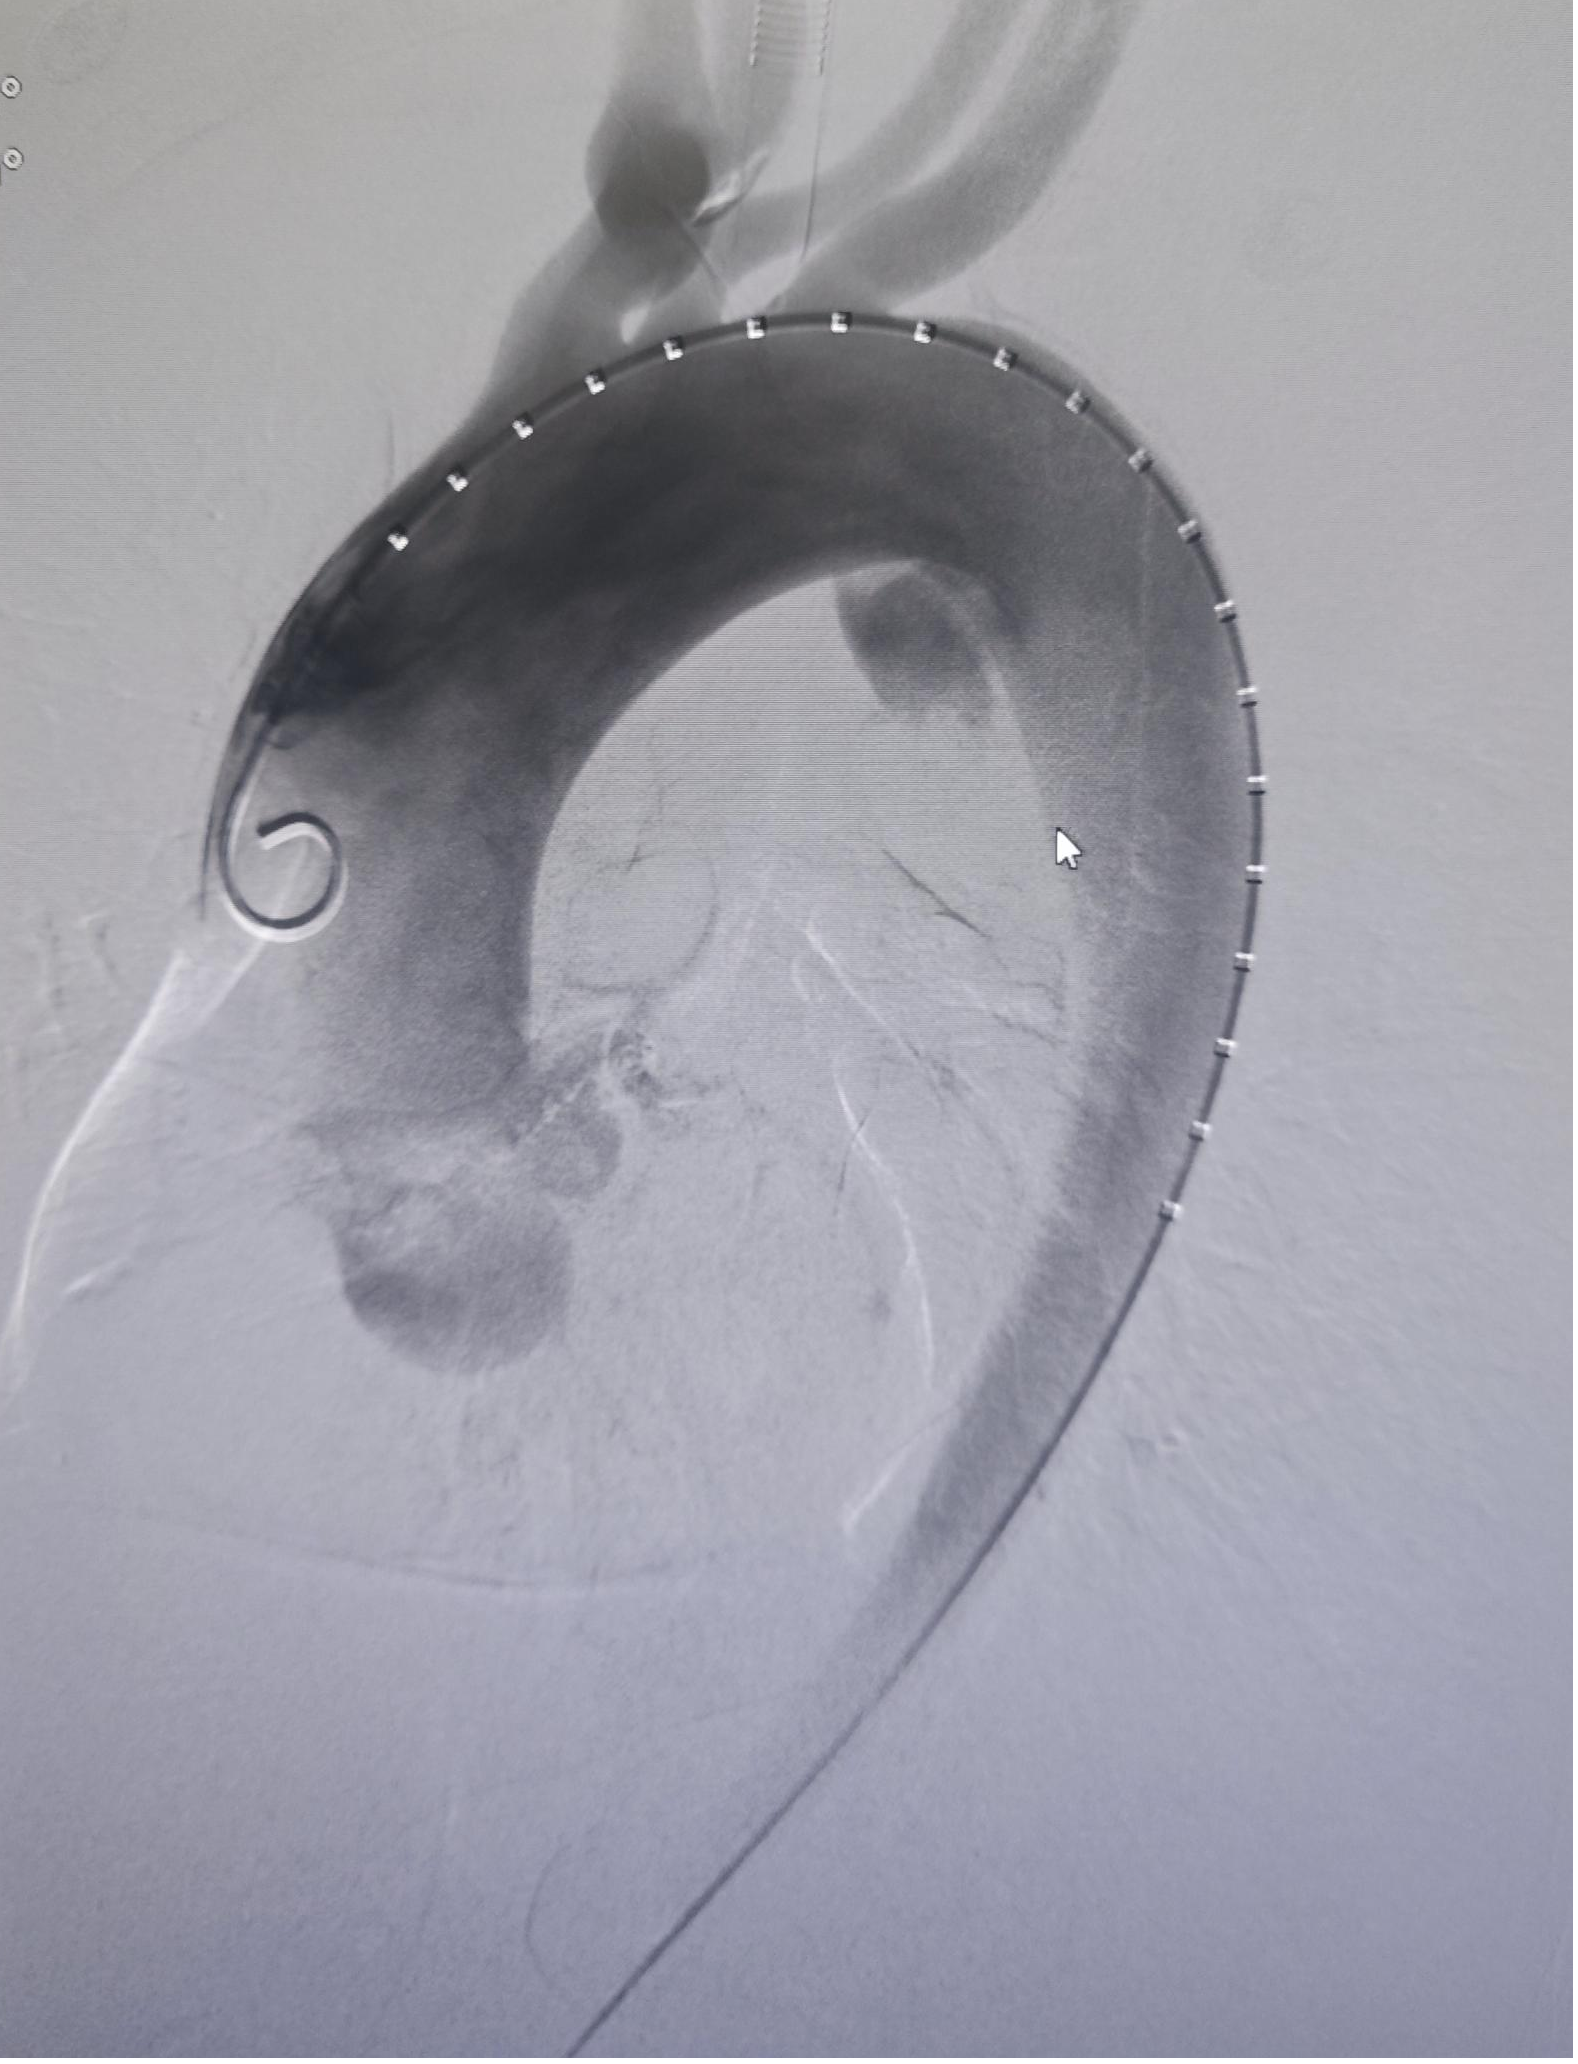

手术期间,术中造影清晰显示出主动脉夹层破口。团队按照术前规划对覆膜支架完成体外开窗操作,随后精准锚定并释放支架。术后造影验证显示,患者夹层破口封堵良好,左锁骨下动脉等分支血管血供正常,手术圆满成功。术后患者恢复顺利,生命体征平稳,仅1天便能下床活动。

术中造影可见主动脉夹层破口